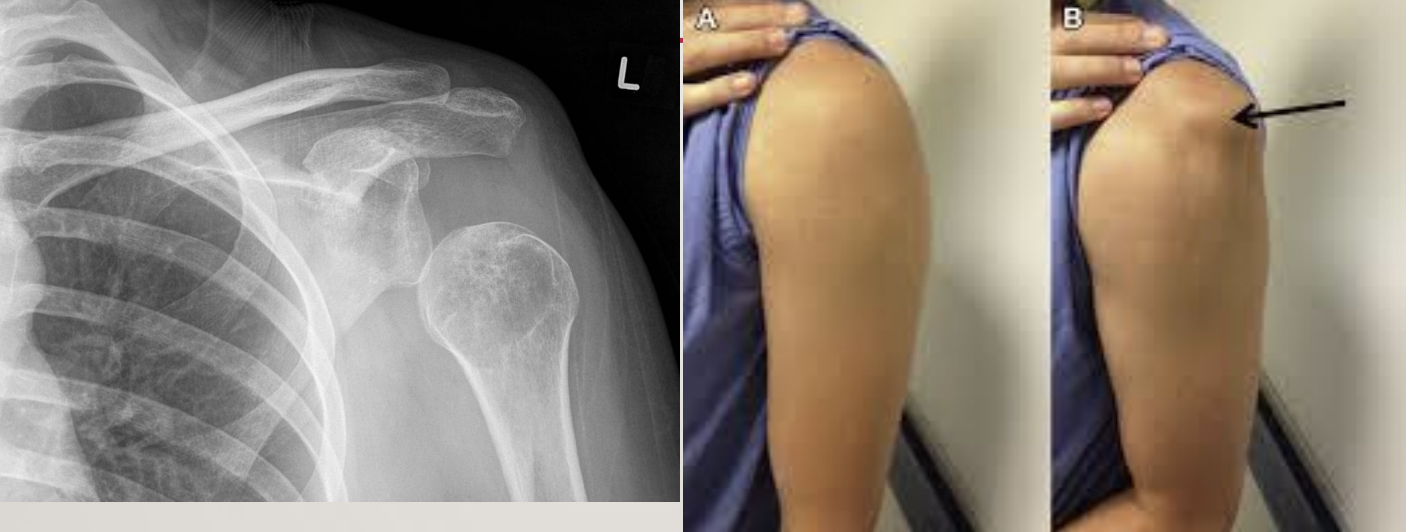

LOSS OF SCAPULAR ALIGNMENT AND CONTROL

1. Resting position of scapula (i.e., appropriate alignment)

2. Function of the scapula:

1. stability,

2. support overhead motions,

3. glides to prevent impingement

3. Why does scapula fall out of alignment?

1. Weakness in scapula

1. of upper traps, of lower traps, etc.

2. Muscle imbalance around the scapula

3. Trunk mal-alignment (B in photo)

4. Usually, downward rotation, “tipping”, and winging

1. due to a problem with the serratus anterior

4. What to look for?

1. scapula

2. vertebrae

3. pelvis

<ol><li><p><strong><u>Resting position of scapula</u></strong> (i.e., <strong><u>appropriate alignment</u></strong>)</p></li><li><p><strong><u>Function of the scapula</u></strong>:</p><ol><li><p><strong><u>stability,</u></strong></p></li><li><p><strong><u>support overhead motions,</u></strong></p></li><li><p><strong><u>glides to prevent impingement</u></strong></p></li></ol></li><li><p><strong><u>Why does scapula fall out of alignment?</u></strong></p><ol><li><p><strong><u>Weakness in scapula</u></strong></p><ol><li><p><strong><u>of upper traps, of lower traps, etc.</u></strong></p></li></ol></li><li><p><strong><u>Muscle imbalance around the scapula</u></strong></p></li><li><p><strong><u>Trunk mal-alignment </u></strong>(B in photo)</p></li><li><p>Usually, <strong><u>downward rotation, “tipping”, and winging</u></strong></p><ol><li><p><strong><u>due to a problem with the serratus anterior</u></strong></p></li></ol></li></ol></li><li><p><strong><u>What to look for?</u></strong></p><ol><li><p><strong><u>scapula</u></strong></p></li><li><p><strong><u>vertebrae</u></strong></p></li><li><p><strong><u>pelvis&nbsp;</u></strong></p></li></ol></li></ol><p></p>